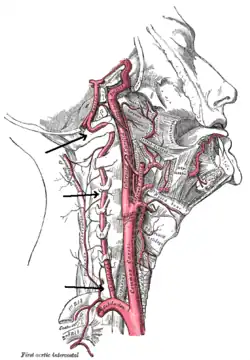

| Arteries of the neck. | |